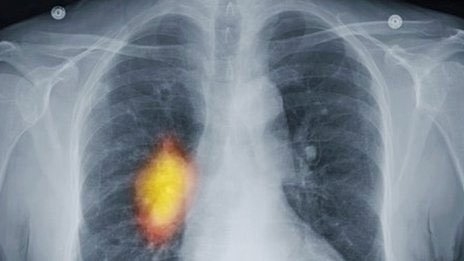

| X quang của bệnh nhân ung thư phổi |